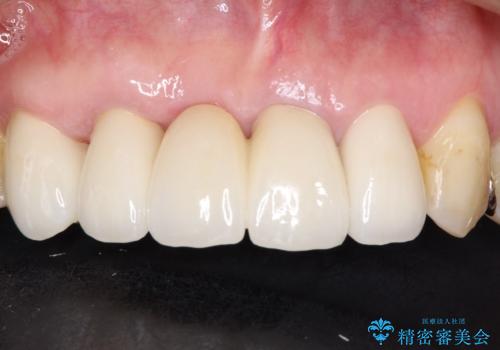

1年程度の治療期間が必要となりましたが、仕上がりには患者様に満足していただけました。

矯正を併用した前歯のセラミックブリッジ治療